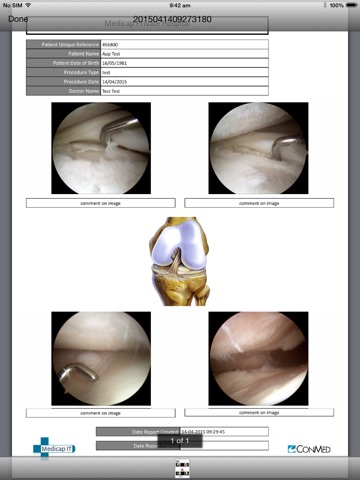

The Medic App is an app for surgeons who utilise Medicap Surgical documentation and recording system. Stream surgical images, video and reports directly to your own personal Apple device to browse or consult with your patients. Save content and take it away with you by simply saving the content to your iPad.

The Medic App is an effective tool for any surgeon or hospital staff member to transport and share content from our servers.